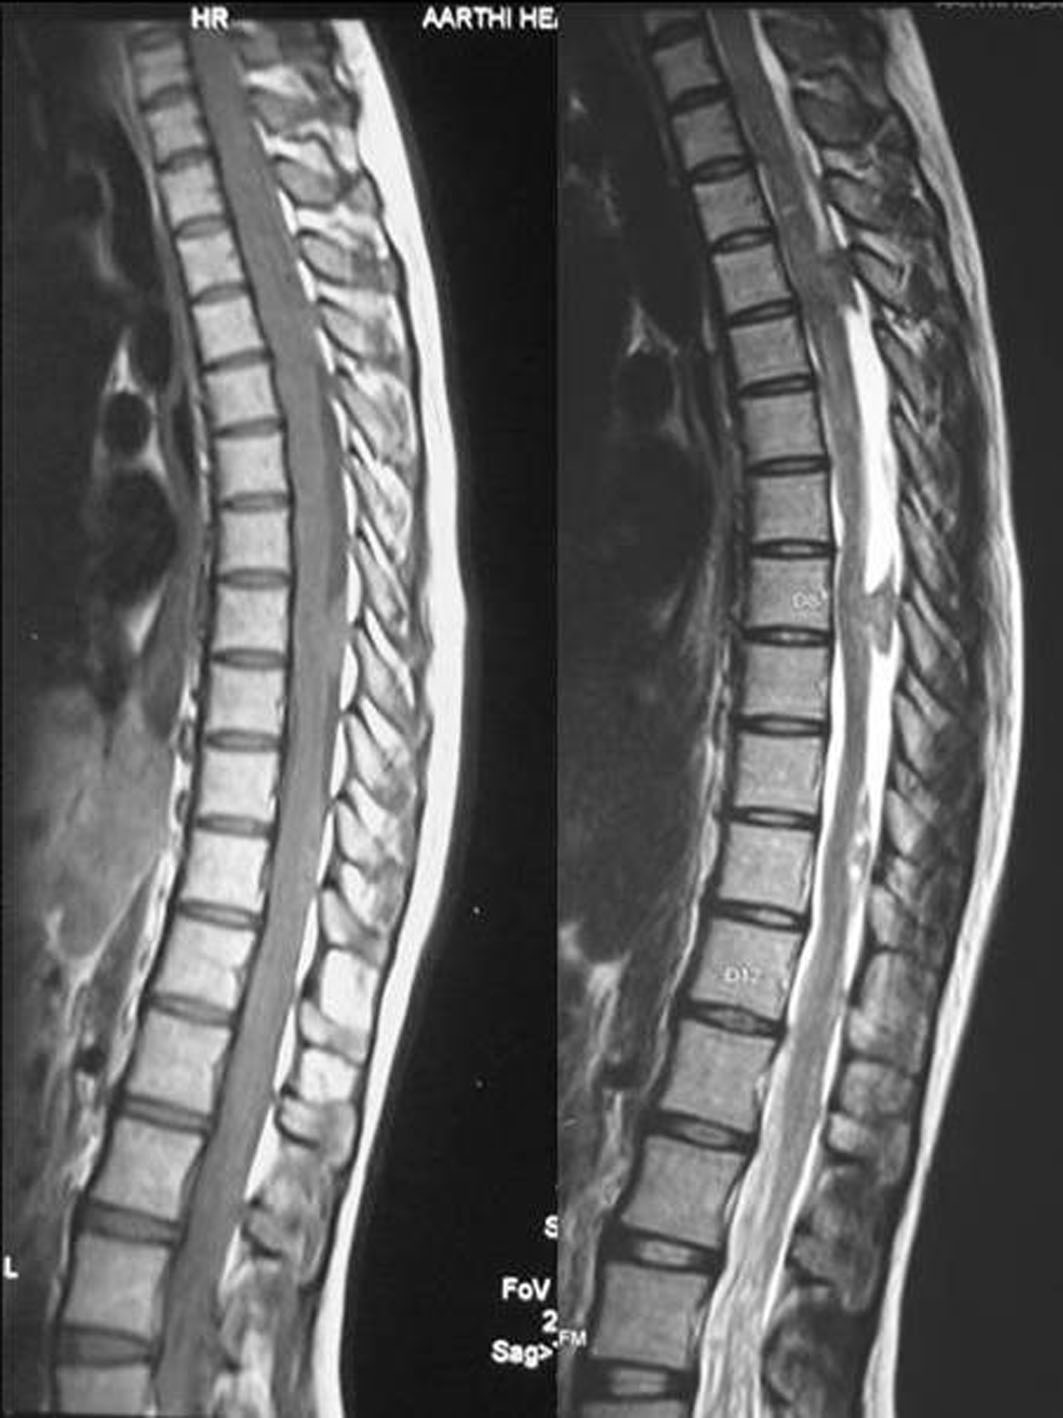

MRI scan of the spine revealed multiple intradural extramedullary spinal lesions at D3-D4, D8 and D10-D11. All the lesions were isointense on T1W and hyperintense on T2W with no significant enhancement with the contrast (Fig. 3).

![]() Click for large image | Figure 3. MRI scans of the spine (sagittal view) showing multiple intradural extramedullary lesions at D3-D4, D8 and D10-D11 which were isointense on T1W and hyperintense on T2W. |